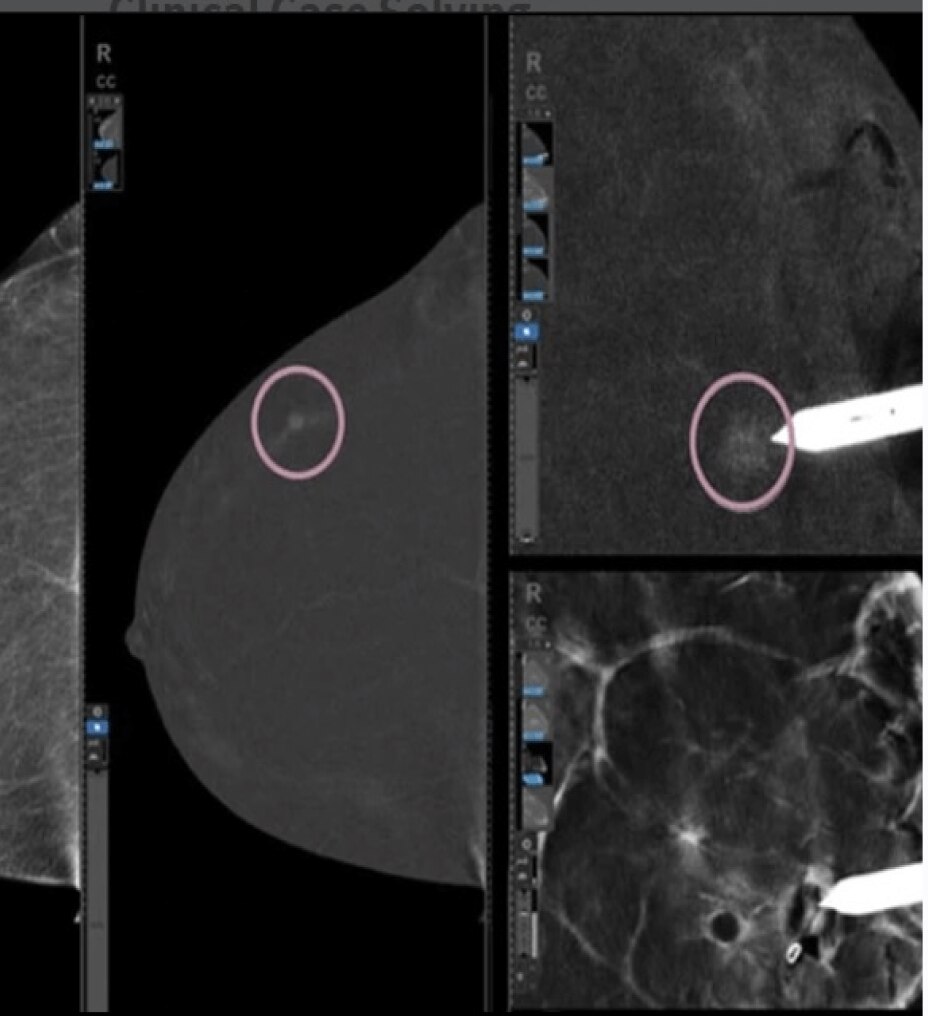

Elevata qualità delle immagini

Grazie alla tecnologia di Deep Learning AIR Recon DL puoi ottenere immagini nitide in tempi rapidi.